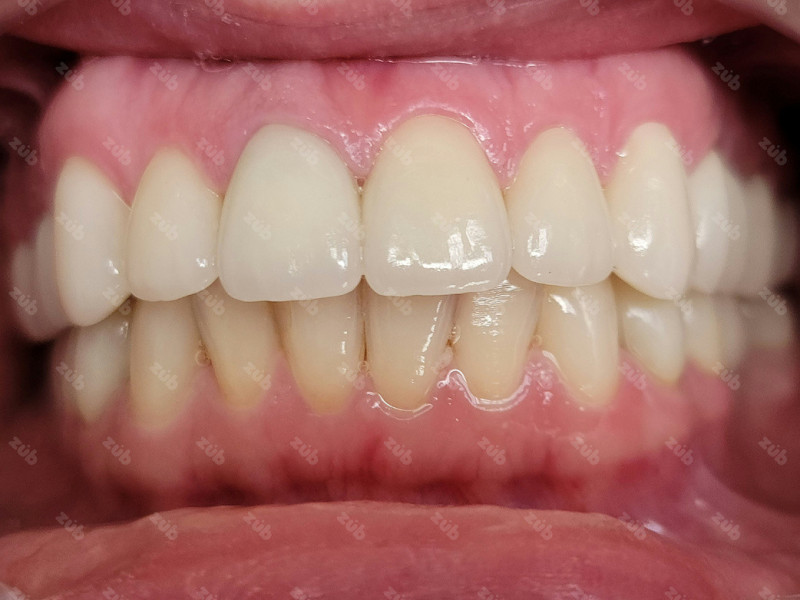

Стоматология ЗУБ (ZUB)

Профгигиена

Все работы клиники